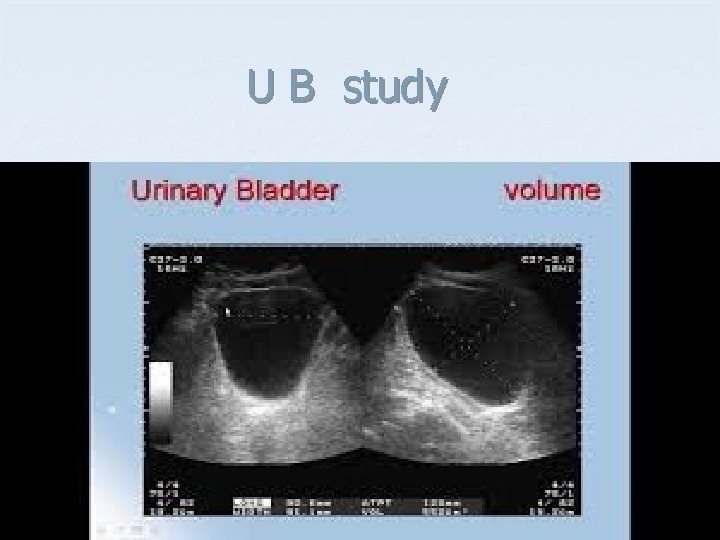

U B study